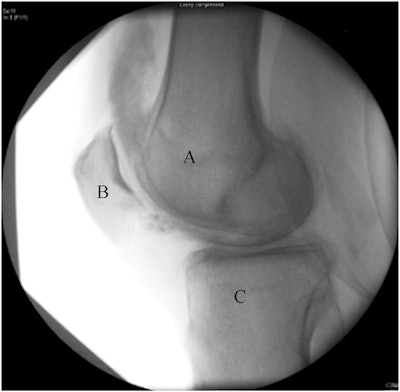

Analysis of the images showed that injectate placed in the suprapatellar recess using the ultrasound-guided technique disperse from the suprapatellar recess into the tibiofemoral or patellofemoral joint after a brief walk with a sensitivity of 96.3% and specificity of 50%, the researchers wrote.

"Fluoroscopic imaging confirmed that ultrasound-guided injection of hyaluronic acid into the suprapatellar recess dispersed into the tibiofemoral joint after a walking test," the authors wrote.